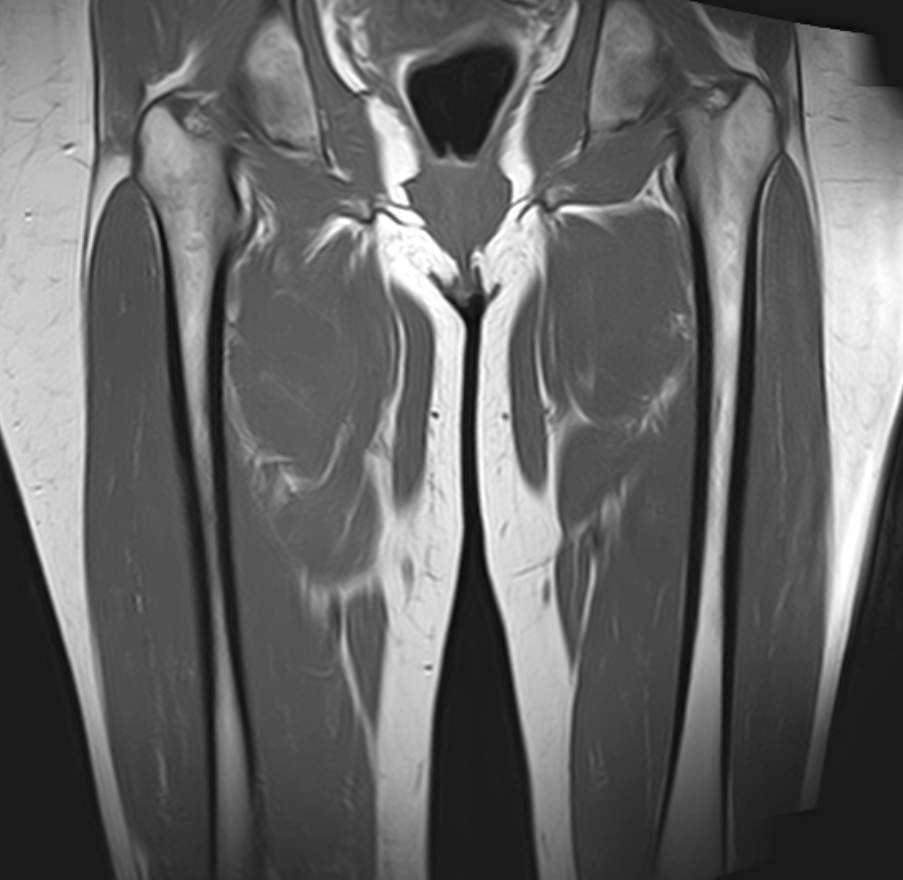

Магнитно-резонансная томография применяется для обследования мягких тканей верхних и нижних конечностей, включая кожу, подкожно-жировую клетчатку, мышцы, фасции, межфасциальные пространства, сухожилия, связки, сосудистую систему, лимфоузлы и лимфатические протоки, нервные волокна, надкостницу и костный мозг.

При проведении МРТ используется действие внешнего магнитного поля без применения вредного рентгеновского излучения, что делает процедуру безопасной для организма человека. Помимо безопасности, достаточной быстроты и неинвазивности метод обеспечивает высокую степень визуализации мягкотканных структур по сравнению с другими исследованиями, например, обычным рентгеном, КТ или УЗИ.

Кроме того, имеет значение показатель индукции магнитного поля томографа. Наша клиника оснащена современным высокопольным томографом последнего поколения TOSHIBA VANTAGE TITAN 1,5 Тесла. Высокая индукция магнитного поля обеспечивает повышенную четкость изображений при обследовании мягких тканей конечностей. За счет послойного сканирования в различных плоскостях с шагом от 1 мм и последующего преобразования данных в объемные изображения томограф обеспечивает выявление мельчайших изменений в тканях. Это позволяет проводить диагностику различных заболеваний на самых ранних стадиях.